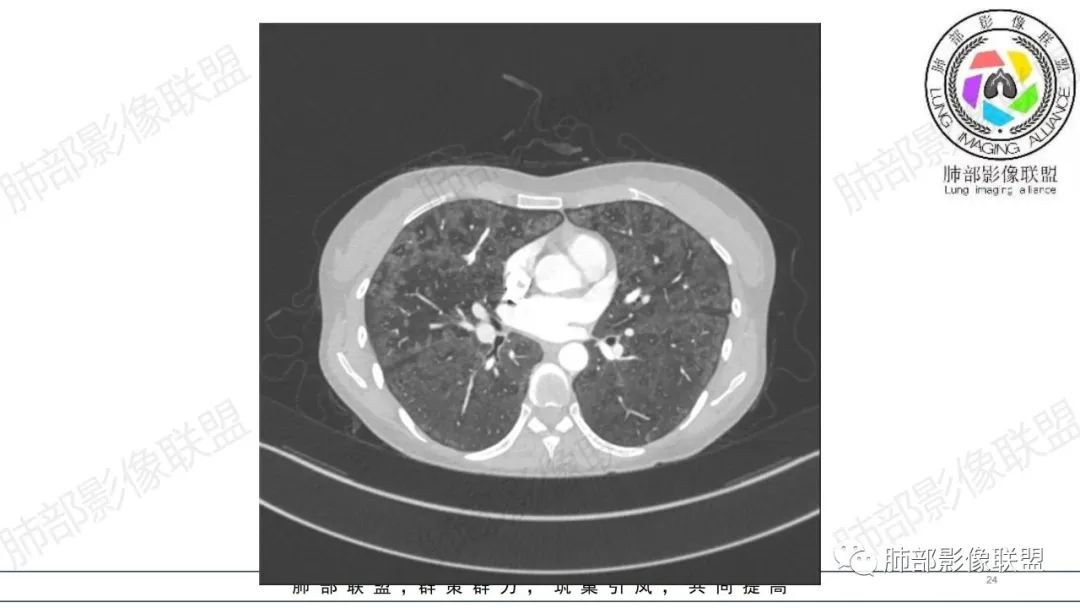

影像资料

34岁女性患者,“哮喘”病史30年,近期有可疑刺激性气体吸入史;因乏力半年,咳嗽、憋气、发热4天就诊;6.1CT提示双肺广泛毛玻璃影及粟粒样结节,胸膜下闲置及血管周闲置,可见树丫征,部分小叶间隔增厚。考虑:1.过敏性肺泡炎,有可疑刺激气体接触史,胸膜下闲置,广泛毛玻璃影,地图样分布,粟粒结节边界模糊,支持过敏性肺泡炎,但糖皮激素治疗效果不佳,且动态复查血常规血红蛋白进行性降低,过敏性肺泡炎 不符合;2.肺含铁血黄素沉积症:患者30“哮喘”病史,可能为肺含铁症状,肺部CT提示双肺弥漫毛玻璃影及粟粒结节影,中下肺明显,肺底部分小叶间隔增厚,近期咳嗽、憋气、发热,血常规血红蛋白进行性下降,考虑肺含铁急性期症状,但临床无咯血症状,肺含铁不典型。综合考虑:肺含铁血黄素沉积症>过敏性肺泡炎。

年轻女性 ,急性喘息发热,肺部影像弥漫磨玻璃密度,部分细小腺泡结节,胸膜下黑线显示,短期复查,病变密度增高,下肺明显,血管周围肺组织累及较少、且逐渐成小叶间隔分布。考虑弥漫肺泡内病变,并经淋巴道转移,下肺比上肺明显,多为免疫细胞功能下肺较强。1.过敏性肺泡炎,有相关病史,三层密度特点、头尾测分布,符合。2 肺泡微石症,多有钙化,且缓慢起病,病程不太符合,放待排。3 吸入相关肺损伤,有病史,疾病演变过程也符合渗出-肉芽肿改变,建议详细询问病史。4 感染性病变,结核?病变气道分布为主,如此弥漫且没有树丫不符合。5.巨细胞病毒,可以磨玻璃 结节 改变,没有免疫缺陷病史。最后考虑吸入所致 1过敏性肺泡炎、吸入性肺损伤 鉴别肺泡微石症。

肺内气腔磨玻璃结节,肝脾肿大,治疗后间质改变,弥漫大B可能